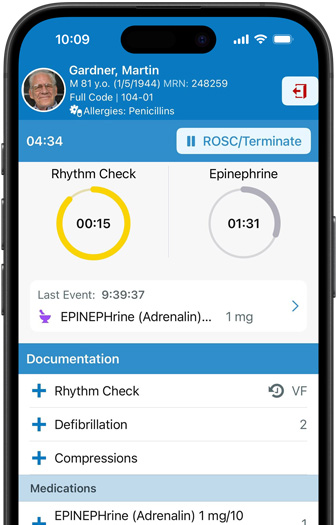

Epic Hyperspace 可協助醫護人員快捷又輕鬆地存取和更新病人記錄。透過使用 AI 技術驅動的臨床摘要、善用 AI 起稿的回應來回答病人訊息,以及診療環境文件記錄,為下一步做足準備。

iPhone 和 Apple Watch 上的 Epic Haiku & Limerick 讓獲授權的臨床醫生可在 iPhone 上安全地存取病人記錄。使用 Epic Limerick,實時更新及通知可在 Apple Watch 及 iPhone 上顯示。

為 iPhone 而設的 Epic Rover 為護士提供順暢的通訊及文件記錄工具。